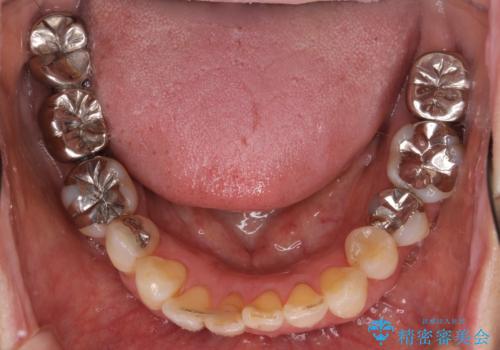

精査したところ右下の奥歯も歯周病により保存不可能な状態でした。

なるべく予算を抑えたいとのご希望から、上顎は入れ歯、右下臼歯部はインプラントによる治療を行いました。

しっかりと咬むことができるようになり喜んで頂けました。

全体的な歯の動揺もなくなり安心して頂けました。

4年経過しましたが問題なく調子が良いとおっしゃって下さいました。

左下のインプラント治療もご希望され、現在治療中です。

インプラントの種類:スプラインツイスト